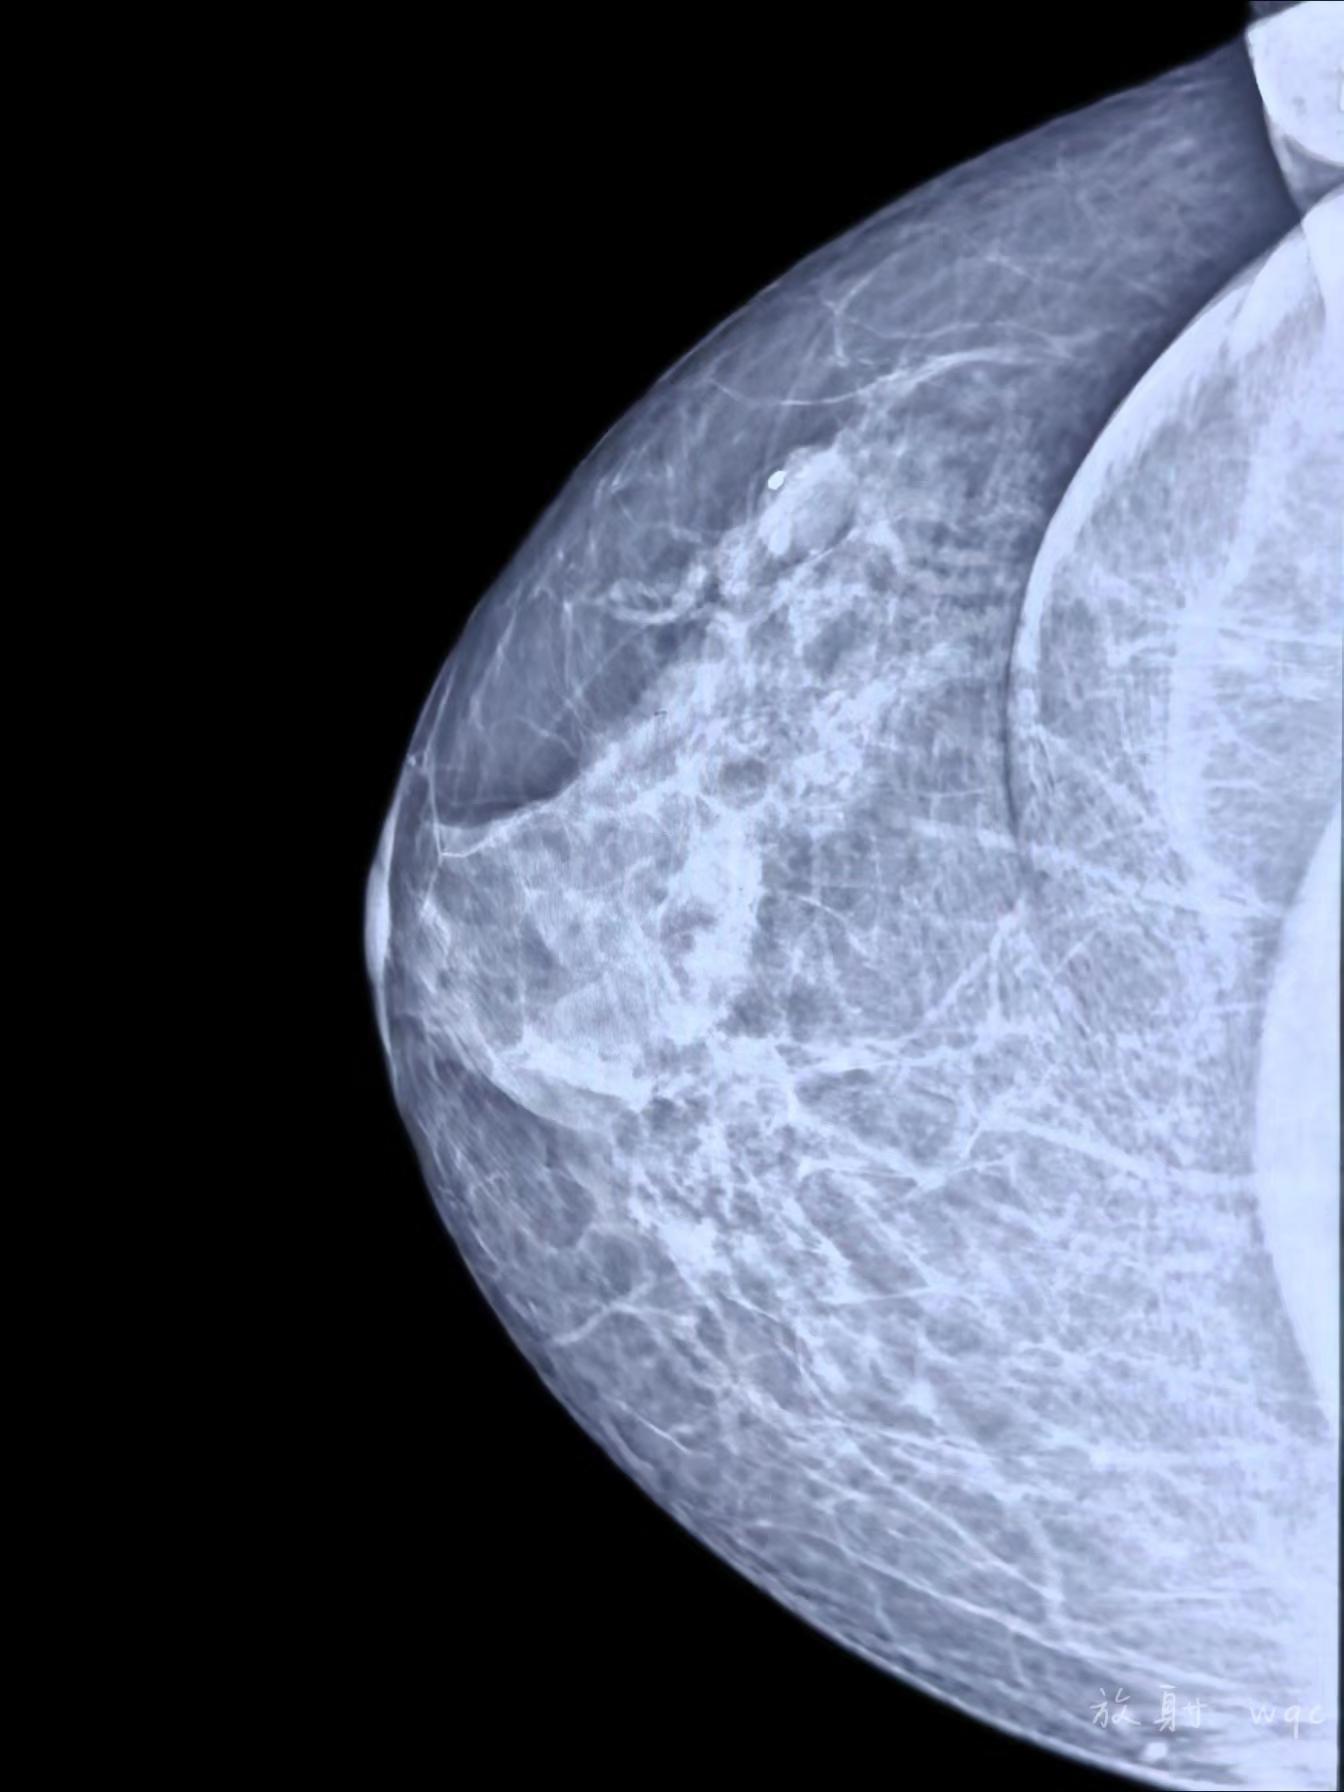

良性还是恶性?